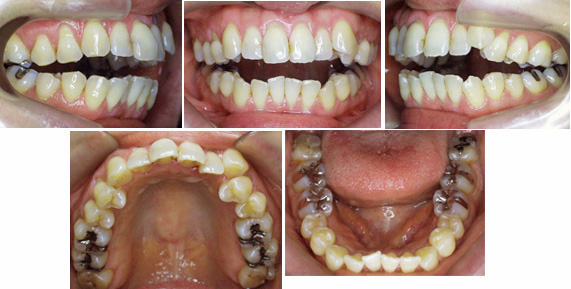

治療例No.66 前歯部開咬 大臼歯1歯しか噛んでいません

来院時の写真

この患者さんも前歯どころかほとんどの歯が噛んでいません。

前から6番目の第一大臼歯だけが噛んでいて

後の歯は噛んでいません。

上下前歯が前方に傾斜しています。小臼歯を4本抜歯して治療しました。同時に担当を決めて筋機能訓練をおこないました。リンガルブラケットで矯正治療しました。

抜歯部位 : 上下顎両側第一小臼歯

治療に使用した装置 : リンガルブラケット